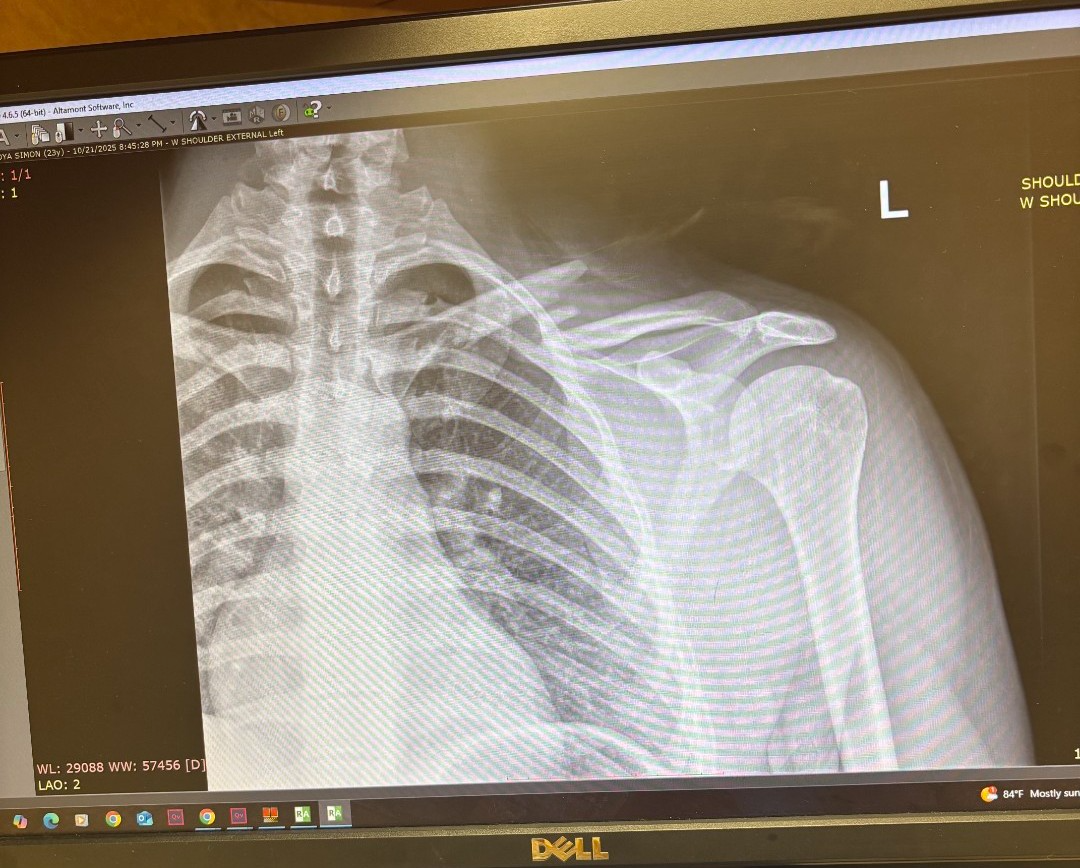

Hello, my name is val and I'm creating a gofund me for my younger brother Simon, who had an accident, unfortunately while training he broke his collarbone in two places and required surgery with plate and screws, along with a physical therapy. He won't be able to work for 10 weeks and the medical bills will be coming soon, that he won't be able to pay, our family is trying our best to help but it isn't enough, if you can help to contribute I would greatly appreciated it.